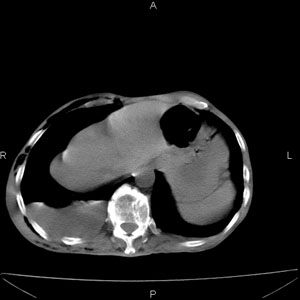

患者男,77岁,于3日前从树上摔下,头部查ct示蛛血,硬膜下出血,上腹部ct未见明显异常,右侧胸腔积液,左侧如常。肺部拍片示右侧肋骨多发骨折住院后今日来查肺部ct,我看到的是1。右侧胸腔血气胸并右肺上叶,中叶压缩性肺不张,2。右肺下叶肺挫伤并多发肋骨骨折,肌内及皮下积气3。左侧少量胸腔积液,我想请教的是3天前左侧胸腔里没有积液今天怎么出现了呢,是什么原因呢?请讨论。

回复楼主   左侧液气胸,液体来源1、肯定有血液成分,多少不一定。2、胸膜腔渗液,由于肺压缩、活动度下降,肯定胸膜吸收有问题,导致积液增多。

因为3天前病人刚摔的时候,左侧胸腔受伤不严重,故而当时没有胸腔积液,但病人受到这么大的伤害,胸膜腔内的液体动态平衡肯定会受到影响,所以过一段时间后才出现胸腔积液。

考虑外伤性迟发性胸腔积液。

右侧液气胸,胸膜创伤、肺组织挫伤,渗出属正常反应。